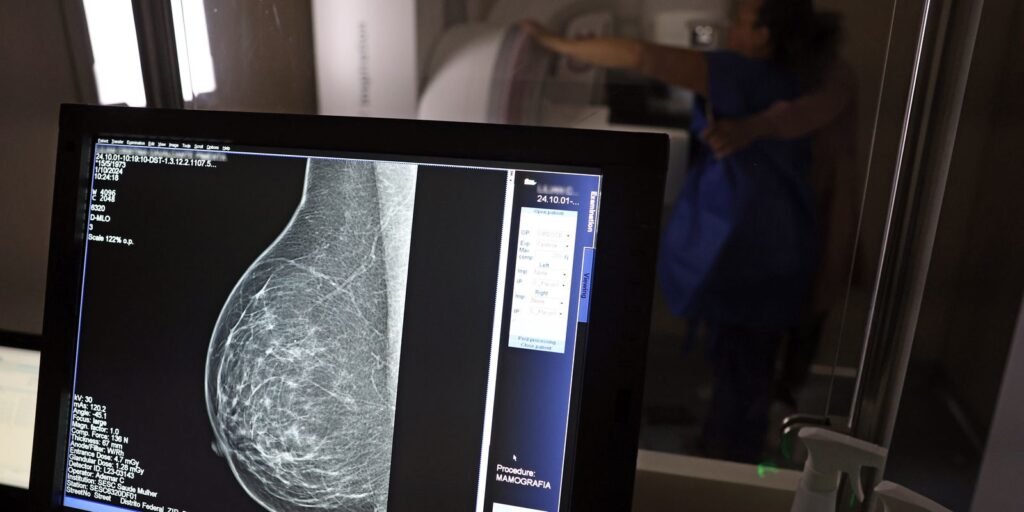

A detecção precoce é a chave para a sobrevivência ao câncer de mama. Contudo, muitas mulheres têm o tecido mamário denso, o que pode dificultar a identificação do câncer de mama por meio da mamografia. Um estudo liderado por pesquisadores da Mayo Clinic descobriu que adicionar outro exame, chamado imagem molecular da mama, ou MBI (Molecular Breast Imaging), a uma mamografia 3D, mais do que dobrou a detecção de câncer em mamas densas.

O estudo foi publicado na revista Radiology. De acordo com as estatísticas, quase metade das mulheres com 40 anos ou mais que realizam mamografias apresentam mamas densas. Entre as mulheres em todo o mundo, o câncer de mama é o tipo de câncer mais comum e a principal causa de mortes por câncer, de acordo com o Global Cancer Observatory.

“A mamografia é um exame de triagem importante, que já se mostrou benéfico. Mas aprendemos que, em áreas de tecido mamário denso, os cânceres de mama podem se esconder da detecção na mamografia até atingirem um tamanho avançado. Nossa pesquisa se concentra em detectar os cânceres mais letais, que podem incluir tumores invasivos de crescimento rápido. Se forem detectados mais cedo, provavelmente poderemos salvar mais vidas,” diz a autora principal e Ph. D. Carrie Hruska, física médica em radiologia na Mayo Clinic em Rochester.

Em uma pesquisa conduzida em cinco centros, a Dra. Hruska e sua equipe estudaram 2.978 mulheres, de 40 a 75 anos de idade, com mamas densas. As participantes do estudo receberam dois exames de triagem anuais do câncer de mama, que incluíam a combinação de um exame complementar de MBI e uma mamografia 3D, também conhecida como tomossíntese digital mamária.

Os radiologistas especializados em mama detectaram mais tecido cancerígeno nos exames de triagem combinados de MBI e mamografia do que em qualquer uma das técnicas isoladamente.

“O MBI é uma opção relativamente simples, de baixo custo e segura para mulheres com mamas densas e que buscam um exame de triagem complementar,” diz a Dra. Hruska.